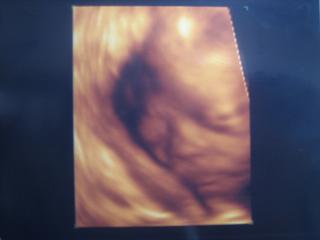

今日は1ヶ月ぶりの妊婦検診

3D(4D?)エコーをしてもらいました

イチゴの時は3Dの機械がなかったので初めての体験です

一番の心配事は「鼻が上を向いてるか!?」だったんだけど

エコーで見る限り大丈夫そうです

イチゴはパパに似て上を向いてるけど、リンゴはママ似かなぁ?

3Dは1回2100円なので結構高い

毎回は無理かな

性別もそろそろ分かるかなと期待してたけど

前回同様逆子状態ではっきりとはわかりませんでした

「女の子かな??」って感じらしい

これからは検診が2週間おきになるんだけど

もし次回も逆子だったら逆子をなおす体操をしないといけないみたいです

前回引っかかった子宮ガンの再検査もして次回まで結果待ちです

昨日はお腹の張りが何度かあってちょい心配

年末年始には何もおこりませんように・・・

3Dの画像です

↓↓↓

顔なんだけどちょうど眠ってたみたい

3Dってリアル